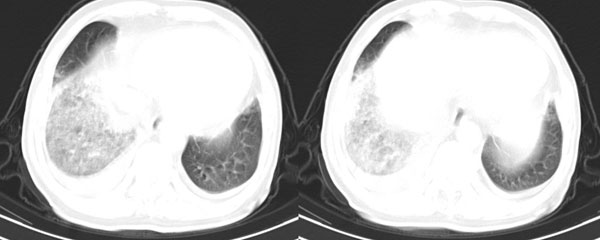

右肺下叶肺野密度增加,呈毛玻璃样密度改变,右恻叶间胸膜有增厚,双恻胸腔有积液.肺内改变我首先考虑是肺泡性肺水肿.

我想楼主发布此病历的目的是要解决右肺下叶磨玻璃样改变是什么原因?我也想知道各位战友和老师从病理生理学的角度对此患者的解释.看了大家的回帖,难免有些遗憾!除了个别老师有些提示外,其余回帖让人觉得有些失望,没有丝毫的营养成分!......

此患者除了双侧胸腔积液外,最明显的病变就是右肺下叶磨玻璃样的改变,如果说是肺泡性水肿,为什么左肺没有改变,一般情况下心衰导致的肺水肿应该是双侧改变呀?我认为还是胸水压迫右下肺膨胀不全合并感染的解释更合理一些!但胸水量比较少,能导致这么明显的肺改变吗?

理论固然重要,但是,既然有人考虑肺不张,那么,哪一段?支气管分叉层面图片没有提供,因此,并不能就此诊断,如果由于腔静脉压迫引起肺通气功能障碍,好像比较少见

心脏肥大,双侧胸腔积液,左肺改变不著,右侧有叶间积液,下叶膨胀不权有可能.